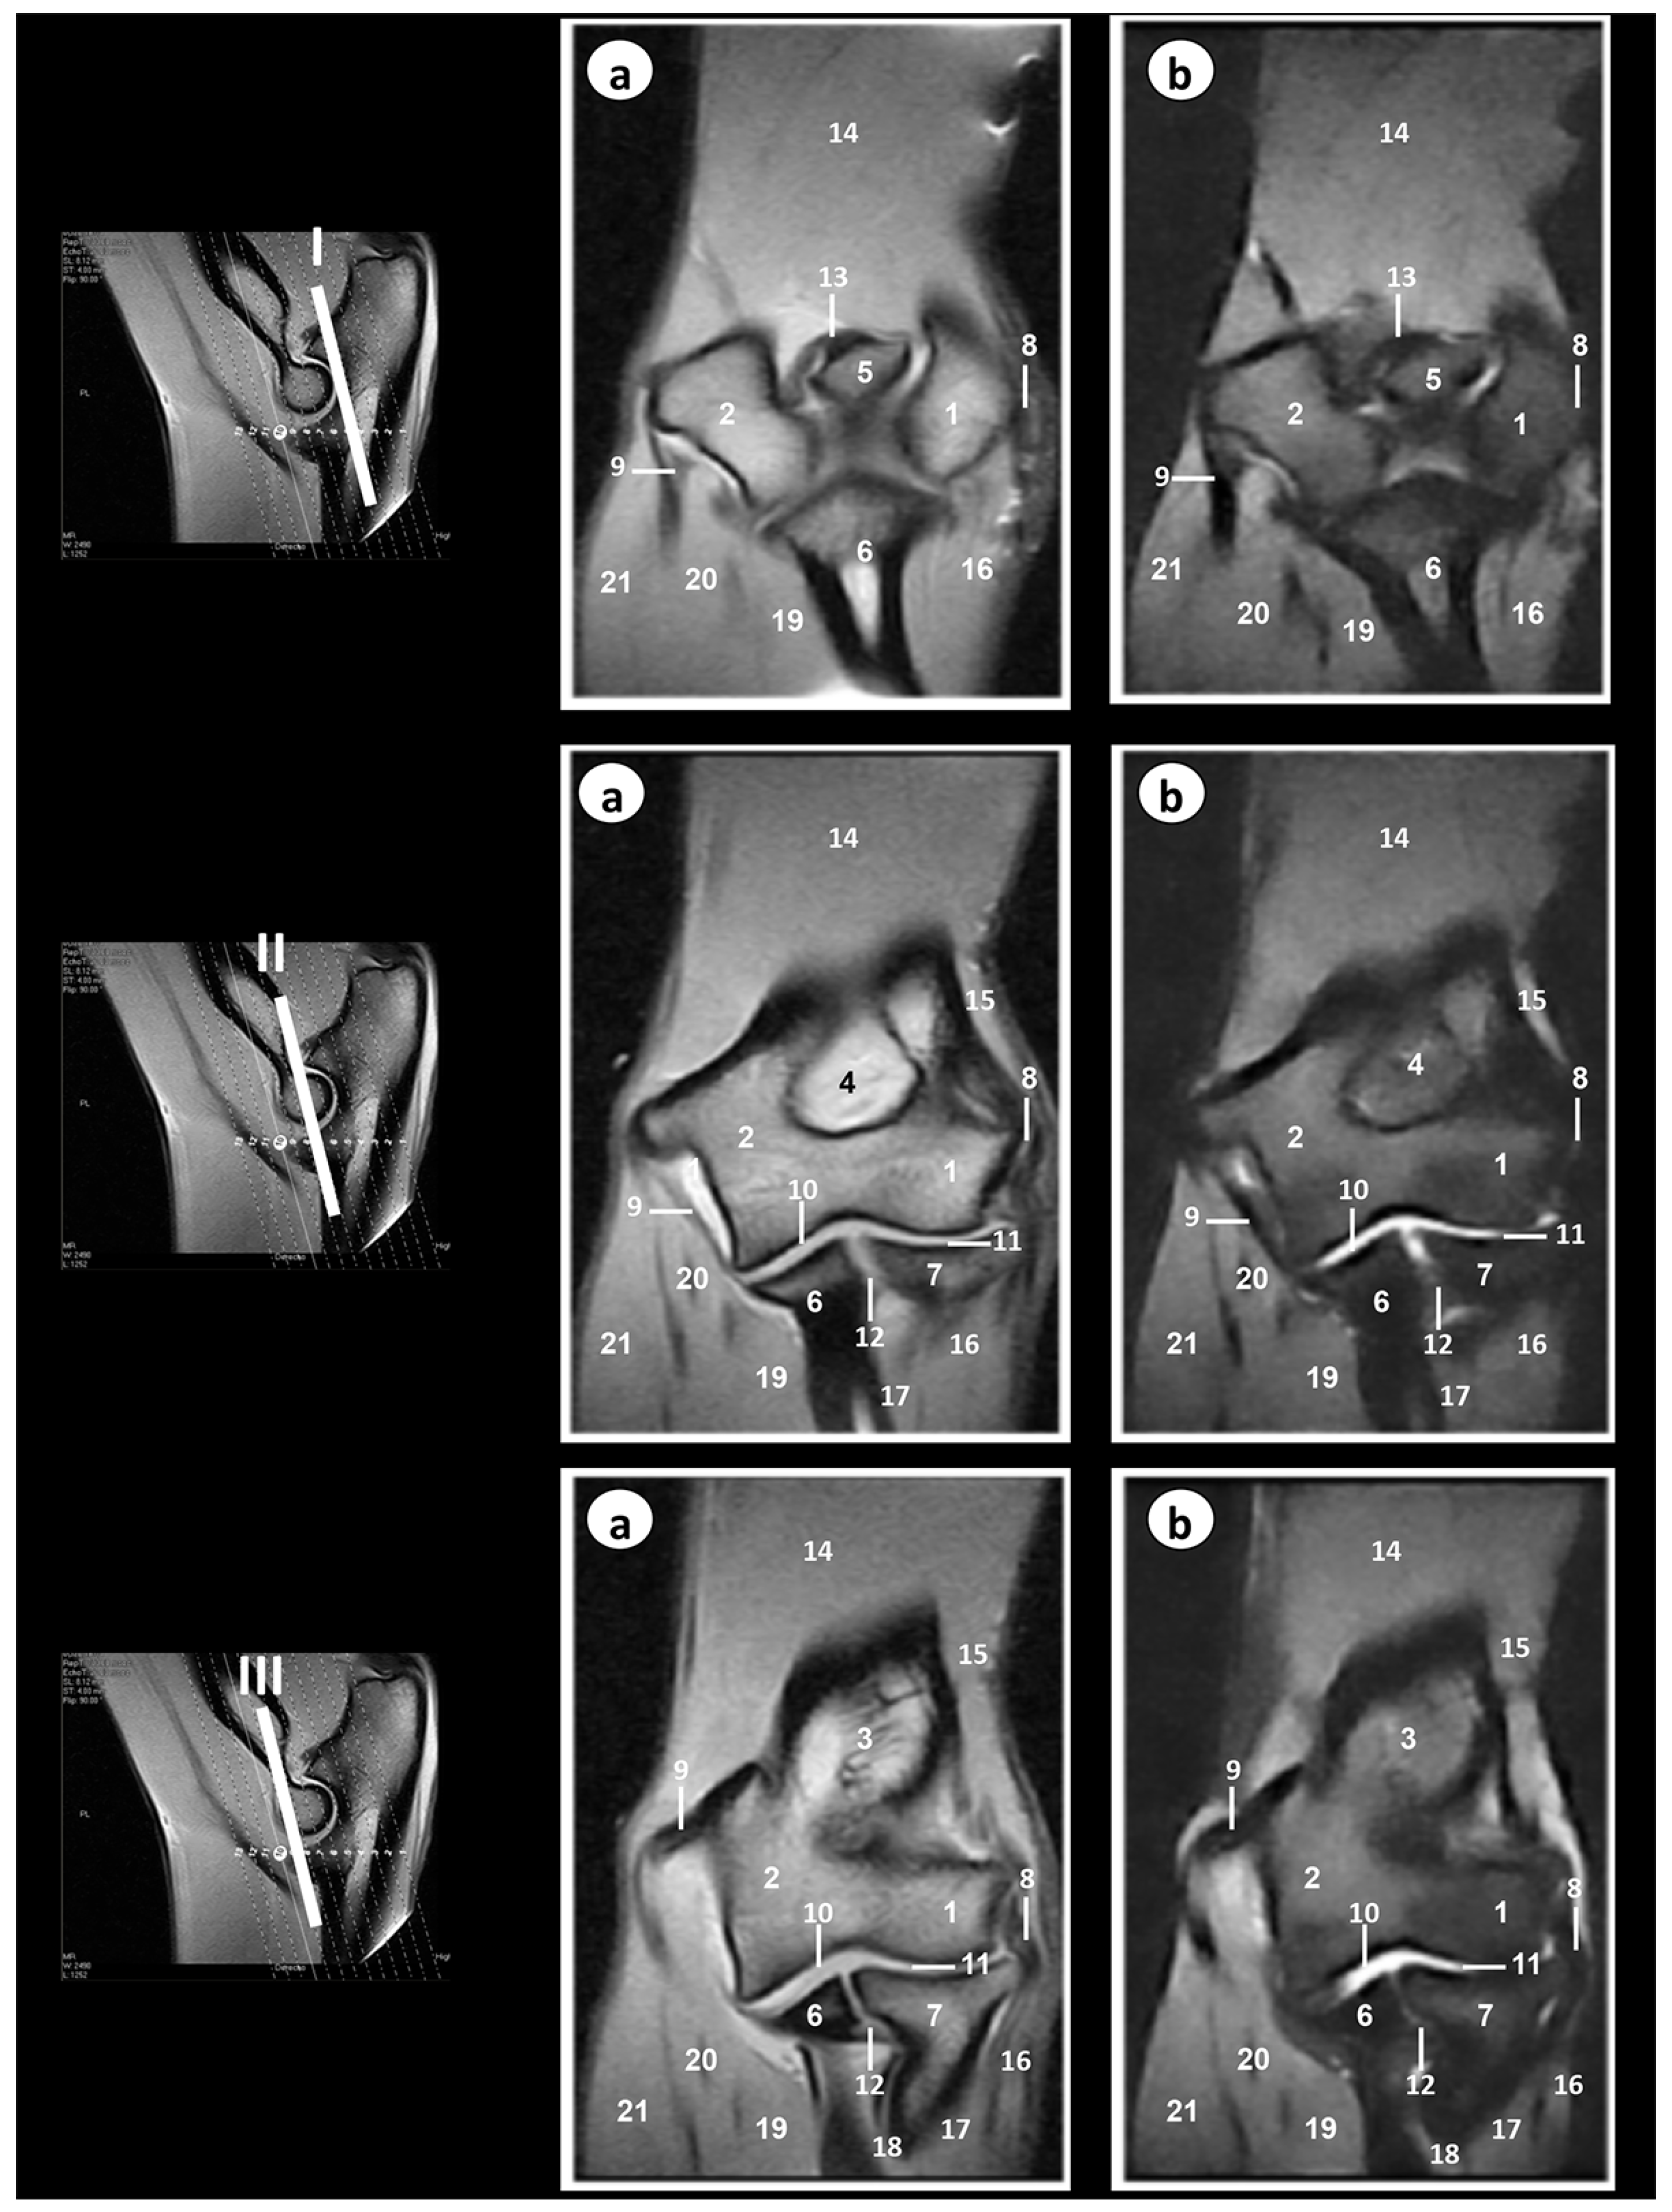

3. Results

3.2. Magnetic Resonance Imaging